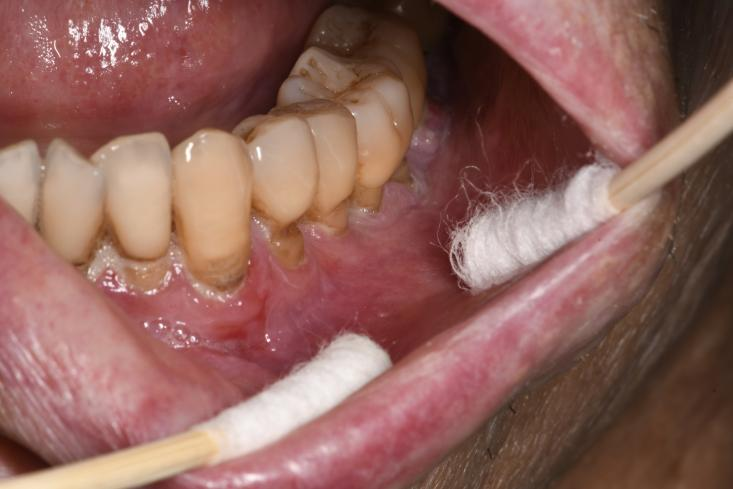

cGVHD不再单纯以移植后100天来划分,而是根据临床表现界定,最早可出现在移植后2个月2,其中45%~83%的cGVHD患者会出现口腔受累,而约20%的患者其cGVHD仅单独表现在口腔3。口腔cGVHD可累及口腔任何部位的黏膜,其特征性表现为口腔苔藓样损害——黏膜上出现网状或树枝状白色条纹4-5,外观类似植物苔藓而得名。在此基础上,病变可表现为黏膜红斑、糜烂、溃疡、假膜形成、萎缩,并伴随小唾液腺囊肿5。患者的主观症状多样,包括但不限于疼痛、口干、味觉改变以及对辛辣、酸性食物的敏感,晚期可出现张口受限6。这些表现并非孤立存在,而是共同构成了一张严重影响患者身心健康的网络。

溃疡形成及苔藓样损害(图片源自陶人川教授团队)